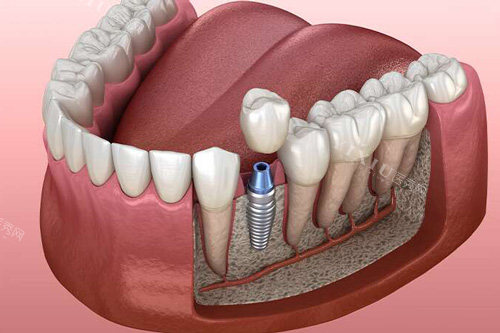

种植牙系列

韩国迪耀种植体:2878-5980元/颗(高性价比首要选择)

韩国登腾种植体:2890-12800元/颗(临床使用率高)

韩国奥齿泰种植体:8000元起/颗

美国进口种植体:9000元起/颗

瑞典诺贝尔PMC种植体:5577-15800元/颗(骨条件适配型)

瑞典诺贝尔种植体:15000-22000元/颗(高端稳定型)